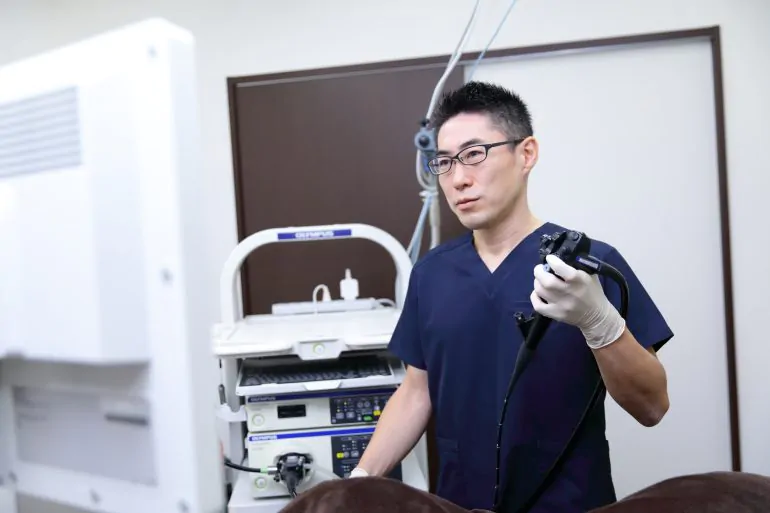

当院の無痛大腸カメラ(無痛大腸内視鏡検査)が選ばれる理由

特徴1、最新鋭の内視鏡機器

内視鏡機器 オリンパス社製、最上位機種「EVIS X1」

おおさわ胃腸肛門内視鏡クリニック品川では、オリンパス社製、最新鋭の内視鏡システム「EVIS X1」を導入しております。「EVIS X1」にはNBI(Narrow Band Imaging)、TXI(Texture and Color Enhancement Imaging)、RDI(Red Dichromatic Imaging)、EDOF(Extended Depth of Field)など新時代を切り開く新たなテクノロジーが詰まっています。検査効率の向上を目指したさまざまな技術を搭載することで、がんをはじめとする、あらゆる消化器疾患を早期発見かつ低侵襲に治療することが可能となります。

おおさわ胃腸肛門内視鏡クリニック品川では、オリンパス社製、最新鋭の内視鏡システム「EVIS X1」を導入しております。「EVIS X1」にはNBI(Narrow Band Imaging)、TXI(Texture and Color Enhancement Imaging)、RDI(Red Dichromatic Imaging)、EDOF(Extended Depth of Field)など新時代を切り開く新たなテクノロジーが詰まっています。検査効率の向上を目指したさまざまな技術を搭載することで、がんをはじめとする、あらゆる消化器疾患を早期発見かつ低侵襲に治療することが可能となります。